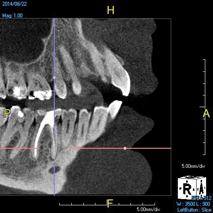

The idea that a dentist may be incorrect in his or her diagnosis is distasteful, but a reality that this profession wrestles with on a daily basis. An image comparison can help to clarify this thought. The first image is a 2D radiograph of tooth No. 19 that includes the buccal cortical plate the lingual cortical plate and approximately 10 mm of trabecular bone compressed into a single image (Figure 1). Because the full width and volume of the tooth is included in the image, any existing pathoses could be masked or hidden in a fog of digital information. A CBCT scan of the same tooth provides more detail because it can present a slice (0.1 mm) of information from the center of the area in question (Figure 2). All of the extraneous information is eliminated, and the clinician and the patient have a more precise picture to evaluate. Furthermore, a periapical radiograph can be distorted by the angle of the cone to the sensor, whereas a CBCT scan has no distortion and is accurate in all views. With a CBCT scan, the clinician is able to state with certainty that a condition exists, and the patient is able to more clearly understand what his or her condition is when considering the available choices for treatment.

(1. ) Two-dimensional periapical radiograph of tooth No. 19 compared with a CBCT scan slice (0.1 mm) of the same tooth, which reveals a well-defined lesion that a patient can more easily understand.

Figure 1

(8.) An original finding of a small lesion on the mesial root of tooth No. 30 was not accompanied by any outward symptoms; therefore, the patient delayed pursuing treatment. When a follow-up CBCT scan was acquired 6 years later, the easy-to-visualize increase in the dimensions of the lesion motivated the patient to elect a treatment plan.

Figure 8

(9.) An original finding of a small lesion on the mesial root of tooth No. 30 was not accompanied by any outward symptoms; therefore, the patient delayed pursuing treatment. When a follow-up CBCT scan was acquired 6 years later, the easy-to-visualize increase in the dimensions of the lesion motivated the patient to elect a treatment plan.

Figure 9